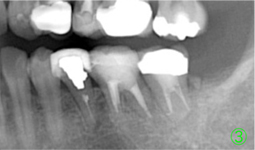

第二大臼歯の歯根が割れていたため、その後ろの親知らずを移植する(①)。親知らずの移植直後(②)。

移植から10年が経過。(③)今のところ問題なく機能してくれている。